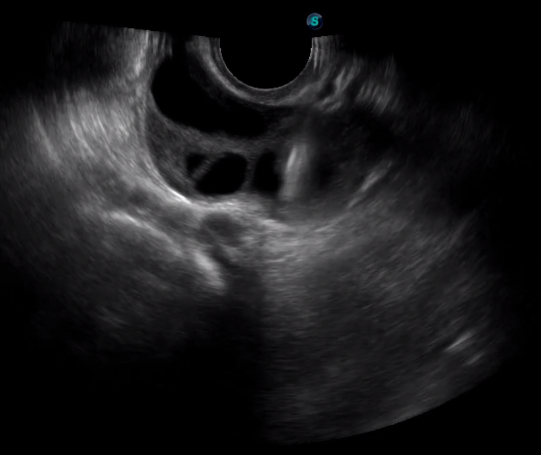

胎移植臨床圖

多數(shù)的生殖科醫(yī)生對(duì)于受精卵的植入采用憑經(jīng)驗(yàn)操作或是使用傳統(tǒng)腔內(nèi)探頭引導(dǎo),同樣存在手術(shù)空間小、受精卵放置位置不確定等風(fēng)險(xiǎn)。專業(yè)的宮腔專用探頭,配合專用的窺器使用,為醫(yī)生提供最大的手術(shù)視野。